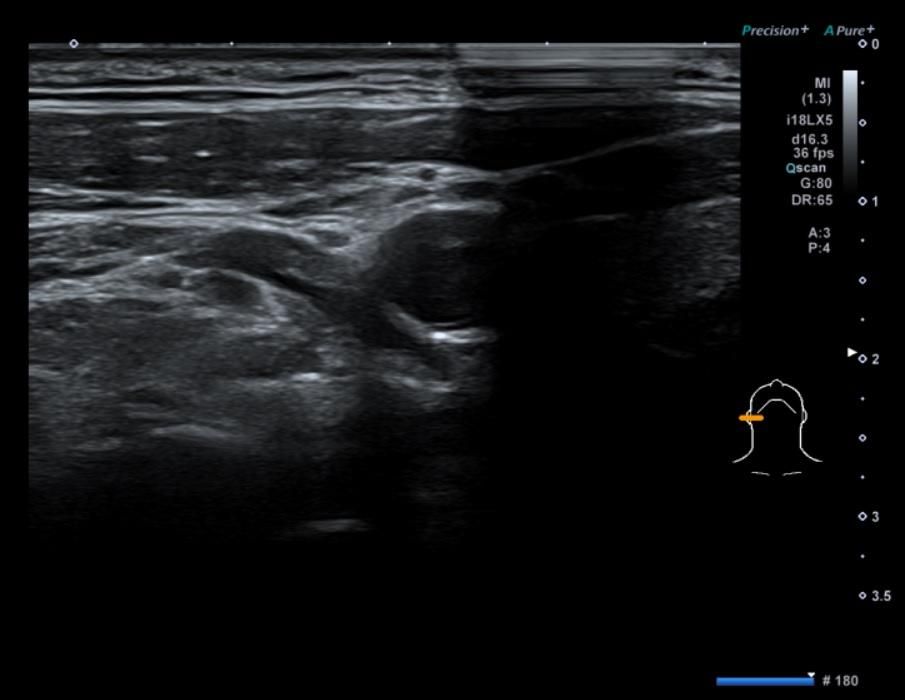

• 2번 째 사진